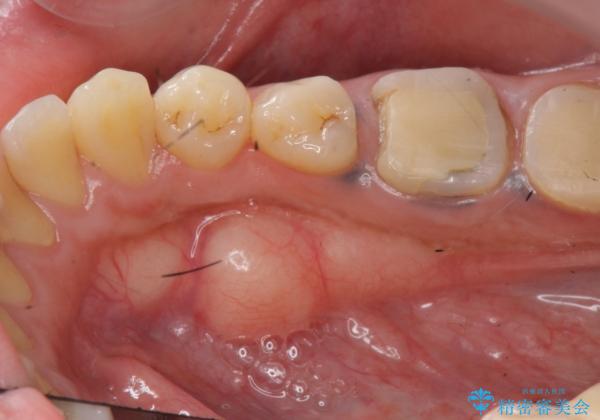

{ 歯周外科 } 骨隆起除去を含む歯冠長延長術

歯周外科を行うことで、歯ぐきの位置を下げ歯の高さを作り出し安定したクラウンの装着が可能となります。また同時に舌の邪魔となっていた骨隆起の除去を行うこととしました。

- 37.4万円(ジルコニアクラウン×2・仮歯×2・歯周外科手術)費用は治療当時の料金となります